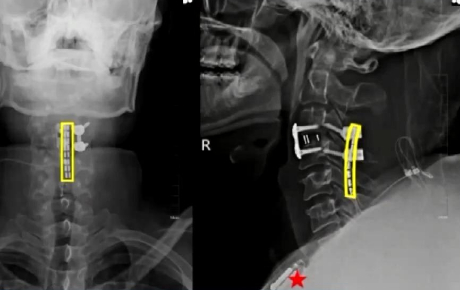

面对这一严峻挑战,医生吴敏飞团队作出了大胆尝试:将脊髓接口技术直接应用于患者颈髓段。吴敏飞介绍,颈脊髓损伤意味着大脑与脊髓之间的联系完全中断。而脊髓接口技术通过在损伤部位精准植入微型电极装置,激活并控制肢体运动神经元,使患者能够重新支配瘫痪的肢体活动。

手术取得圆满成功。经过两周持续优化的精准神经调控,刘博奇的四肢肌力显著恢复。三个月后,团队为他量身定制了“脊髓接口+外骨骼机器人”协同康复方案。在脊髓接口的精准调控与外骨骼机器人的辅助支撑下,刘博奇成功迈出了受伤后的第一步。